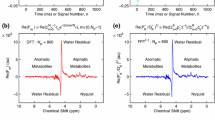

Second, the T2 relaxation times of the metabolites were calculated using the data of all volunteers combined for the FID and for each echo. These six pooled spectra (1 FID and 5 echoes) are shown in Fig. 2. It can be observed that the phosphomonoesters decay much slower than the phosphodiesters. T2 decay plots were made for each of the metabolites, resulting in a T2 relaxation time for PE of 154 ms (95 % CI 144–164), for PC of 173 ms (95 % CI 148–205), for Pi of 188 ms (95 % CI 182–193), for GPE of 48 ms (95 % CI 44–53), and for GPC of 23 ms (95 % CI 21–26). Subsequently, the combined data of the FID and echoes were analyzed, on group basis and on individual basis, accounting for the calculated T2 relaxation times of the metabolites (i.e., the FID and echoes were T2-weighted and summed on a group level and individually). The phosphorus metabolite ratios of these spectra analyzed on group level are presented in Table 1 and Fig. 3. 31P MR spectra, analyzed on group level, in the four phases of the menstrual cycle are displayed in Fig. 4. The results for the seven volunteers individually are displayed in Fig. 3. In the group analysis a negligible variation in metabolic ratios throughout the menstrual cycle is observed, which is similar to the inaccuracy (expressed as standard deviations) of the measurement. The individually analyzed data show more variation between the volunteers as well as between phases in the menstrual cycle within the volunteers; however, the standard variations are larger as well. No specific pattern of variation during the menstrual cycle is observed for any of the ratios, and magnitudes of the observed variations are in the order of the experimental uncertainties (P = 0.86, P = 0.90, P = 0.75, for PME to PDE, PE to GPE, and PC to GPC, respectively).

In previous work, where 31P MRS was similarly assessed in four premenopausal women, the summed data showed PME to PDE ratios of 1.06, 1.75, 0.48, and 0.78 for EF, LF, EL, and LL, respectively [22]. In our study, the summed data showed PME to PDE ratios of 0.75, 0.70, 0.69, and 0.72, indicating a more stable course throughout the menstrual cycle. Furthermore, the reported lower PME peak area in the late follicular phase—as measured in five women by Twelves et al. [23] was not reproduced, nor did we find significant lower levels of the individual monoesters PE and PC in any phase when assessing the metabolic ratios. In contrast to previous work, the SNR in our study was higher, which can be appreciated in the presented spectra. The higher SNR, and also higher spectral resolution provided by 7 T, allowed for assessment of the PE/GPE and PC/GPC ratio as well. Still, the measurements uncertainty, as can be observed by the standard deviations of the ratios, especially in the individual assessment, remains greater than the observed variation.

A relatively low PCr signal can be observed in the presented spectra. PCr has been reported to originate mainly from the chest wall in MRS breast spectra [15, 23]. When chest wall muscle is included a PCr signal a multitude greater than PME, Pi, or PDE is to be expected [15]. A relative low PCr signal is, therefore, considered a marker of good localization.

T2 relaxation times were calculated to account for when using the multi-echo data to maximize the SNR. To accurately determine the T2 relaxation times all data were pooled over the volunteers and time points, assuming that T2 values do not changes over the menstrual cycle. In the calculations the PDEs showed to have a much shorter T2 relaxation time than the PMEs. That could possibly lead to misinterpretation of the multi-echo data when not compensating for this difference.